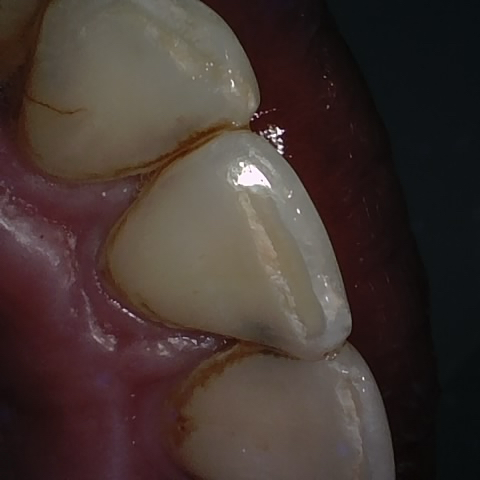

Annotated as "Good"